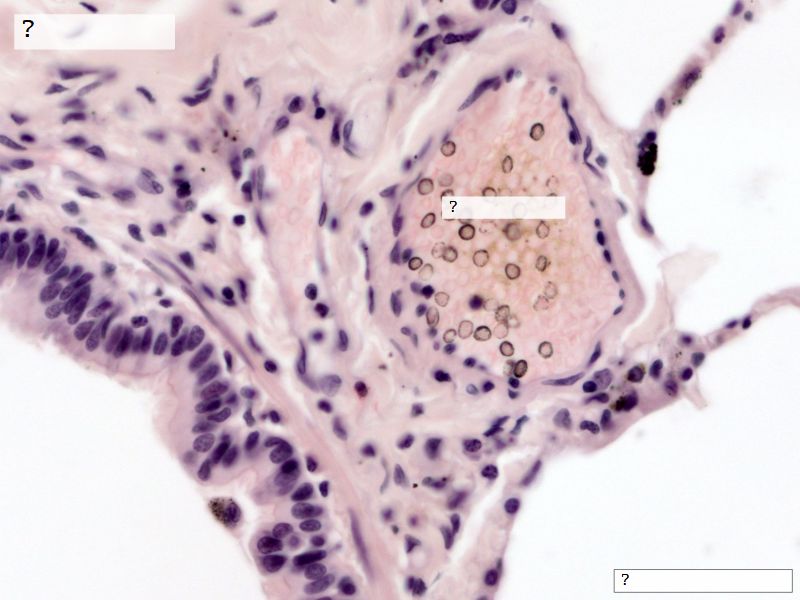

Fill in all the missing labels, and assess as you move through the slides. Answers on the down slide. It is important to do this using pen and paper, and not just glance through the images.